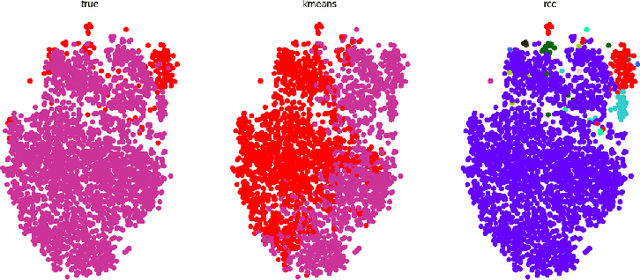

Abstract:With the recent outbreak of COVID-19, creating a means to stop it's spread and eventually develop a vaccine are the most important and challenging tasks that the scientific community is facing right now. The first step towards these goals is to correctly identify a patient that is infected with the virus. Our group applied an unsupervised machine learning technique to identify COVID-19 cases. This is an important topic as COVID-19 is a novel disease currently being studied in detail and our methodology has the potential to reveal important differences between it and other viral pneumonia. This could then, in turn, enable doctors to more confidently help each patient. Our experiments utilize Principal Component Analysis (PCA), t-distributed Stochastic Neighbor Embedding (t-SNE), and the recently developed Robust Continuous Clustering algorithm (RCC). We display the performance of RCC in identifying COVID-19 patients and its ability to compete with other unsupervised algorithms, namely K-Means++ (KM++). Using a COVID-19 Radiography dataset, we found that RCC outperformed KM++; we used the Adjusted Mutual Information Score (AMI) in order to measure the effectiveness of both algorithms. The AMI for the two and three class cases of KM++ were 0.0250 and 0.054, respectively. In comparison, RCC scored 0.5044 in the two class case and 0.267 in the three class case, clearly showing RCC as the superior algorithm. This not only opens new possible applications of RCC, but it could potentially aid in the creation of a new tool for COVID-19 identification.